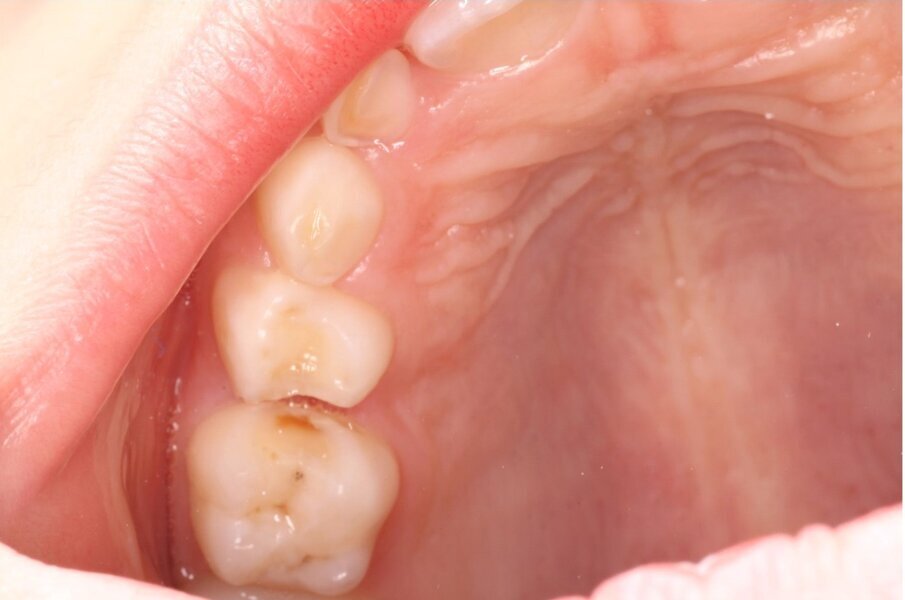

Het eerste kind waarbij wij NRC toepasten was 6 jaar. Op de bitewings werden cariëslaesies bij alle vlakken van de aangrenzende melkmolaren gediagnosticeerd. Met de ouders werd besproken wat onze plannen waren. Zij gingen hiermee akkoord. In de volgende zitting werden de 8 vlakken beslepen (afbeelding 1a-b). De behandeling verliep probleemloos en werd goed geaccepteerd. Maar in het vervolgtraject hebben we steken laten vallen. De voorlichtende communicatie gebeurde hoofdzakelijk traditioneel. De terugkomtermijn besloeg een paar keer achter elkaar een interval van bijna een jaar. Daar verander je geen gedrag mee. De verslaggeving ontbrak een aantal keren. Bijna 6 jaar later werd geconstateerd dat er veel plaque aanwezig was. De wisseling had inmiddels plaatsgevonden. Restauratief of chirurgisch ingrijpen is sinds NRC werd toegepast niet nodig geweest en de bitewings vertonen geen cariësactiviteit (afbeelding 2a-b). Ook waren geen sealants noodzakelijk geweest.

Afbeelding 1a. Beslepen melkmolaren in de bovenkaak (NB het verdient aanbeveling de distale vlakken schuiner te beslijpen dan de mesiale vlakken in verband met de toegankelijkheid voor de tandenborstel).

Afbeelding 1b. Beslepen melkmolaren in de bovenkaak (NB het verdient aanbeveling de distale vlakken schuiner te beslijpen dan de mesiale vlakken in verband met de toegankelijkheid voor de tandenborstel).